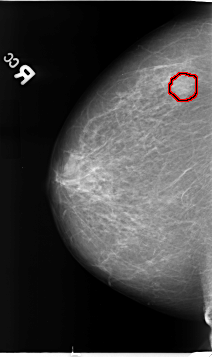

B_3113_1.RIGHT_CC

RIGHT_CC LINES 4640 PIXELS_PER_LINE 2752 BITS_PER_PIXEL 12 RESOLUTION 50 OVERLAY

FILE: B_3113_1.RIGHT_CC.OVERLAY

TOTAL_ABNORMALITIES 1

ABNORMALITY 1

LESION_TYPE MASS SHAPE ROUND MARGINS CIRCUMSCRIBED

ASSESSMENT 3

SUBTLETY 4

PATHOLOGY BENIGN

TOTAL_OUTLINES 1

BOUNDARY